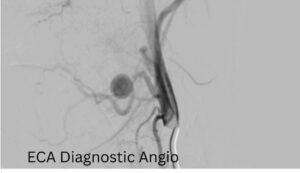

وأكد الدكتور حسان النعماني رئيس الجامعة، أن سرعة التشخيص ودقة التدخل كانتا عاملين حاسمين في إنقاذ حياة الطفلة، مشيرًا إلى أن جاهزية مستشفيات سوهاج الجامعية والتكامل بين أقسامها المختلفة أسهما في التعامل الفوري مع الحالة وفق أحدث الأساليب العلاجية. وأضاف أن فريق الأشعة التداخلية أجرى الفحوصات والأشعات اللازمة فور وصول الطفلة، والتي كشفت عن وجود تمدد شرياني نازف بأحد الشرايين الرئيسية بالرقبة في جدار الحلق، ما تطلب تدخلاً عاجلاً عالي الدقة.

ومن جانبه، ذكر الدكتور احمد كمال المدير التنفيذي للمستشفيات الجامعية، أنه تم تجهيز وحدة القسطرة على الفور، حيث نجح الفريق الطبي في غلق التمدد الشرياني باستخدام حلزونات دقيقة عبر القسطرة التداخلية، مما أسهم في السيطرة الكاملة على النزيف دون الحاجة إلى جراحة تقليدية، وتقليل احتمالات المضاعفات.